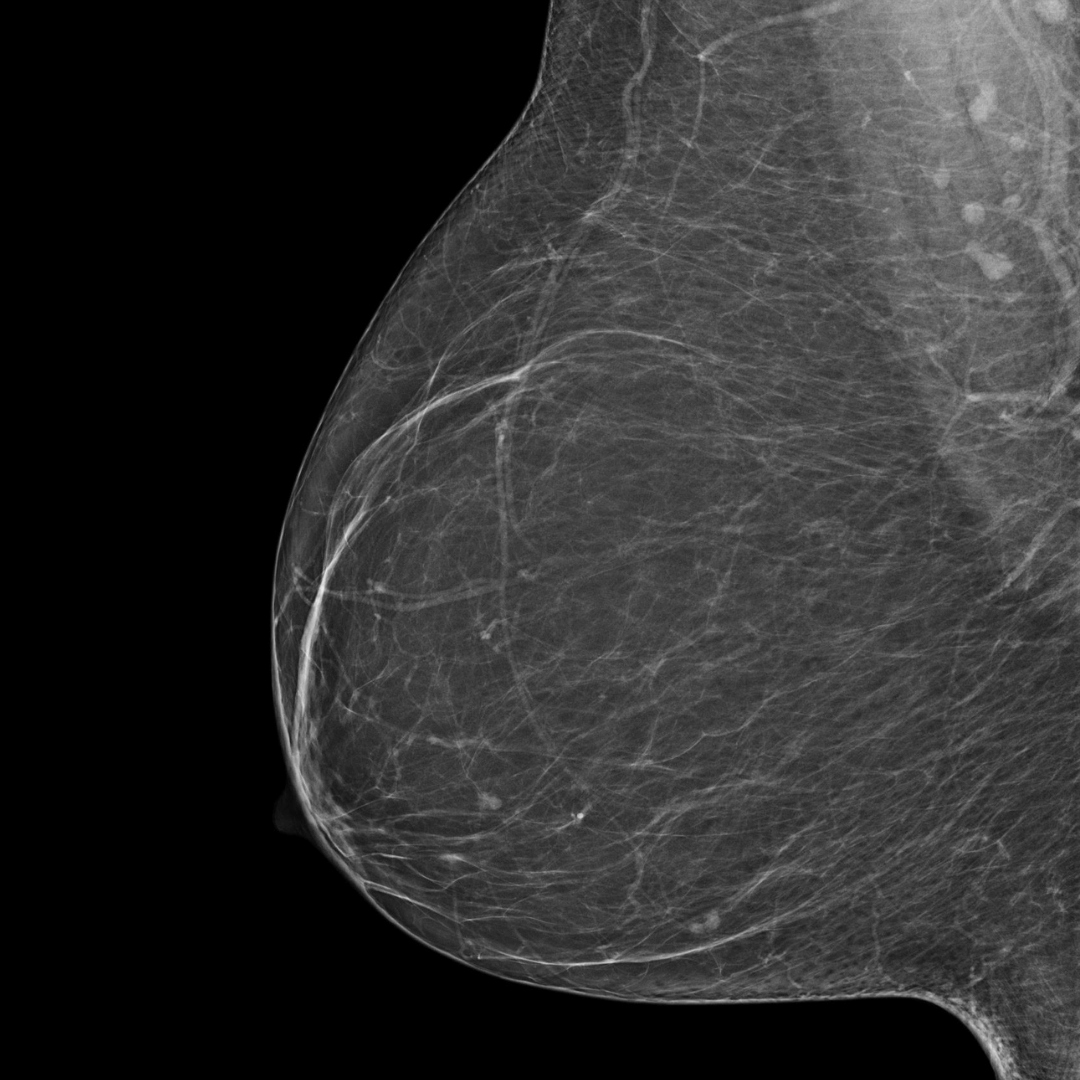

Category A

(least dense)

BI-RADS category A:

The breasts are almost entirely fatty. The breast tissue is not dense.